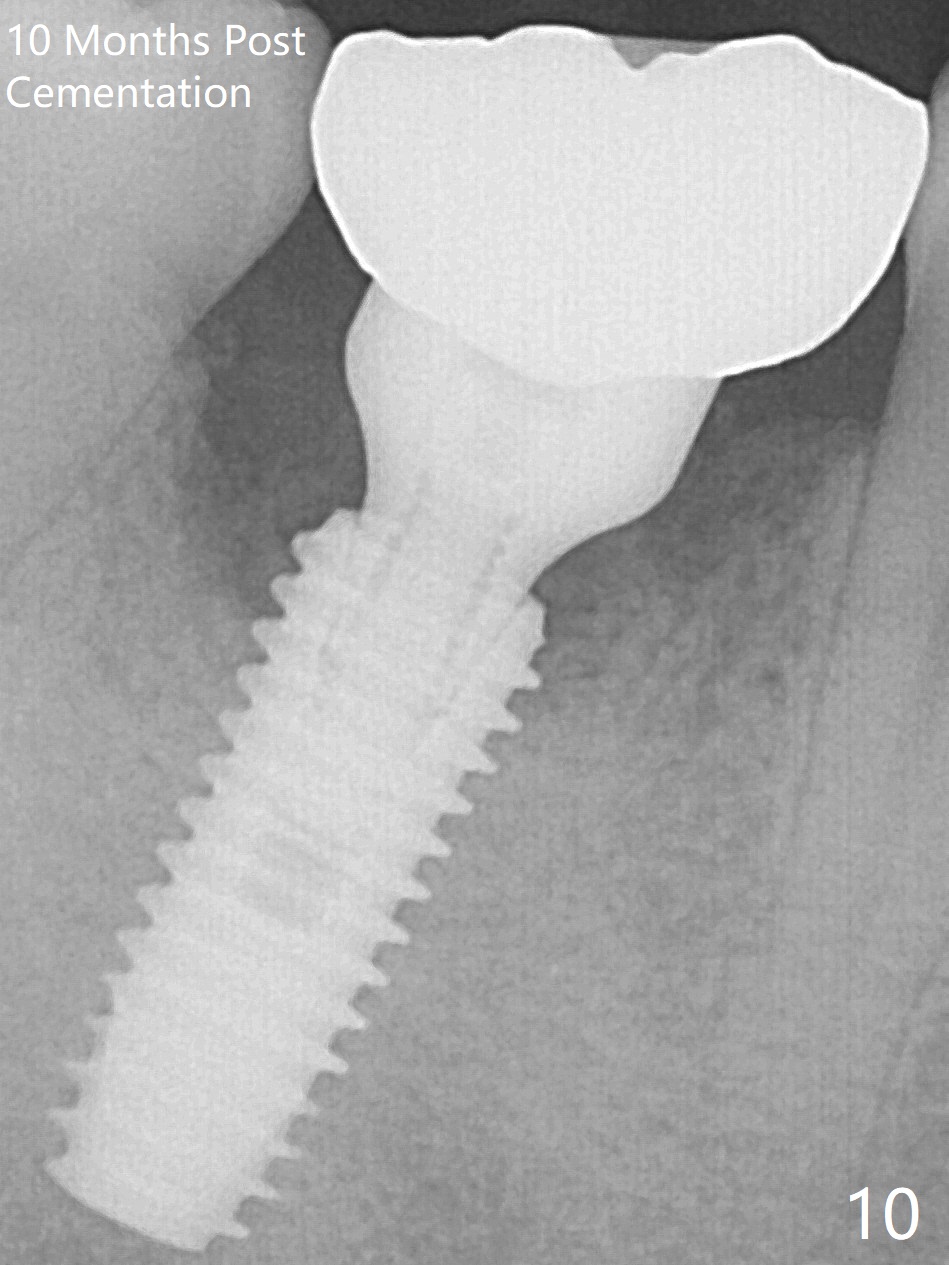

Fortunately no paresthesia is reported postop. Why is the Inferior Alveolar Canal not violated? Fig.7 is a coronal section of CBCT taken for a 40-year-old man at the lower 1st molar (at the septum). At the region, the Canal (brown circle) is close to the lingual plate (L). Because of severe bone loss of the lingual plate of this case (Fig.8 *), osteotomy is intentionally created buccal (green). The deep osteotomy may not contact the Canal, while the hemorrhage may stem from the medullary space (M in Fig.4,7). Bone morphology at the coronal end of the implant apparently changes 4 months postop, suggesting osteointegration (Fig.9). Impression is taken. Bone density around the implant at the crest seems to increase (Fig.10), while there is no soft tissue deficiency 10 months post cementation (Fig.11). The bone appears to regenerate toward the abutment, particularly distally, 14.5 months post cementation (Fig.12). Periimplantitis develops (bleeding on water pik and erythematous and tender buccal gingiva) 1 year 7 months post cementation (Fig.13,14). The 1st three threads are exposed (*). Bone graft with PRF and 6-month membrane or Cytoplast will be needed. Pain disappears 3 days of oral antibiotic. The gingiva looks healthy 1 month later when he returns for bone graft (Fig.15). But the lingual gingival cuff is not so healthy when the crown/abutment is removed (Fig.16 <). Bone graft is not done. For those patients with suboptimal oral hygiene, implants should be placed as low as possible, better with guide for precision.